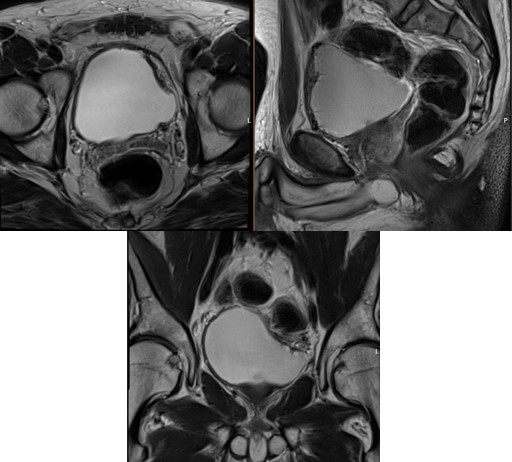

Follow-up at 3 months with MRI and flexible cystoscopy confirmed no evidence of recurrence (Figure 4). The patient maintained a satisfactory functional bladder capacity (300 ml) and reported an International Prostate Symptom Score (IPSS) of 5 with a storage score of 0.

Figure 4: Axial, sagittal and coronal views of T2-weighted MRI of the bladder showing normal bladder wall, with no evidence of local/ regional recurrence.